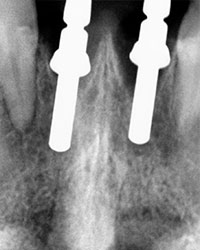

Se toma radiografía periapical con el radiovisiografo, encontrando zona radiolúcida periférica a los dos alvéolos, al retirar la férula los dientes se salen solos en condiciones desfavorables para su reinserción periodontal.

Radiografía Periapical

Dientes Centrales